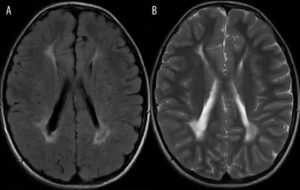

Справочно. Лучше всего визуализируются очаги глиоза на МРТ либо КТ-аппаратах.

Эти современные приборы позволяют с высокой точностью выявить сосудистые изменения, опухолевые процессы, патологические участки в белом веществе лобных долей, очаги кровоизлияний, ишемическое поражение.

Диагностика глиоза головного мозга основывается на данных КТ и МРТ:

- Магнитно-резонансная томография, является приоритетным методом для выявления таких отклонений. Помощью этого метода, специалист увидит очаги глиоза в мозге, выяснит степень распространенности и определит точную причину возникновения болезни.

- Компьютерная томография тоже может быть использована в качестве способа диагностики глиоза белого вещества головного мозга, но данный метод не дает такой точной клинической картины, как МРТ, а кроме того КТ способно облучать рентгеновскими лучами, что сказывается на общем здоровье не лучшим образом.

- В случае глиоза, обычно в заключении МРТ может быть написано – «картина очага глиоза в левой (правой) лобной доли».

- Если очаги множественные, то данная методика выявит все места их локализации и масштабы гибели нейронов.

- Также магнитно-резонансный томограф определит причину возникновения таких очагов.

- Если виновником отмирания нервных клеток стало заболевание сосудистого характера, то в заключении МРТ будет написано – «картина единичного (множественных) очагов глиоза в белом веществе головного мозга – вероятно, сосудистого генеза». Подробнее о сосудистом генезе головного мозга и что это такое читайте в нашей аналогичной статье.

- Кроме того, специалист может выявить дополнительные отклонения в головном мозге, в виде гидроцефалии, гематом и других болезней.